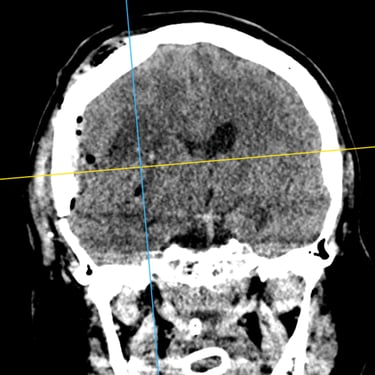

Hemorragia Intracerebral: Craneotomía y Evacuación del Hematoma

La hemorragia intracerebral es una emergencia neurológica grave que requiere diagnóstico rápido y tratamiento oportuno. Cuando el hematoma produce efecto de masa, deterioro del estado de conciencia o riesgo de herniación, la craneotomía y evacuación quirúrgica se convierten en la opción indicada. Este procedimiento permite abrir la bóveda craneal, retirar el coágulo y disminuir la presión intracraneal, preservando la función neurológica. Su objetivo es detener el daño secundario, mejorar la perfusión cerebral y estabilizar al paciente. La intervención temprana, combinada con cuidados críticos especializados, aumenta las posibilidades de supervivencia y recuperación funcional en este tipo de emergencia.